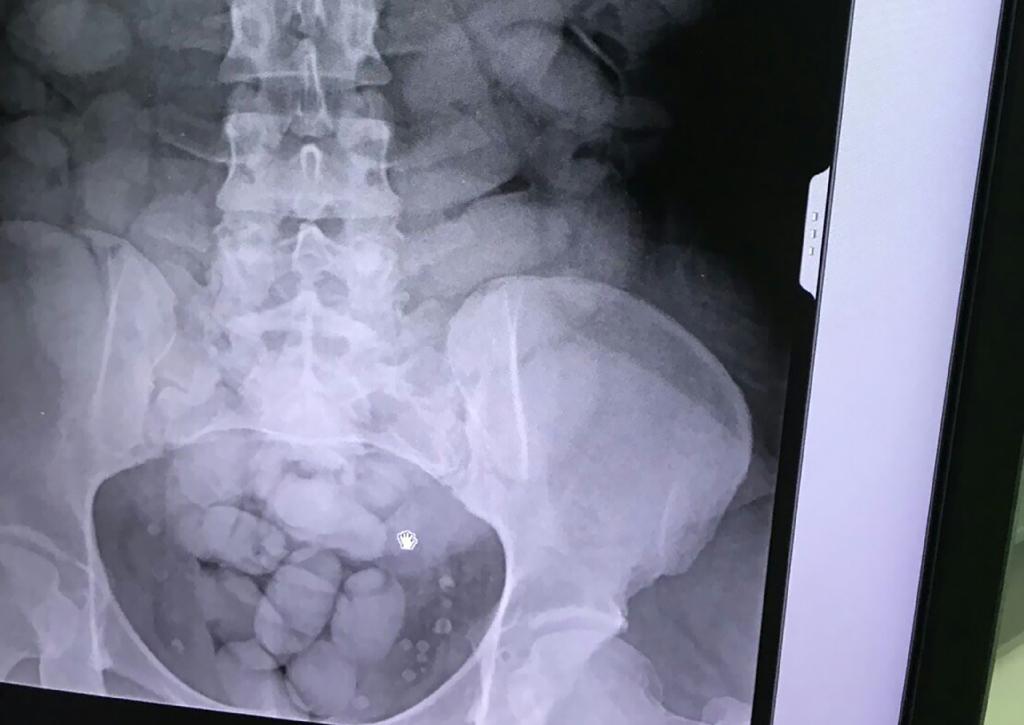

The investigating officer told the court that they had information that Khumalo had ingested 60 sachets with the substance, but had so far has discharged 58 of them.